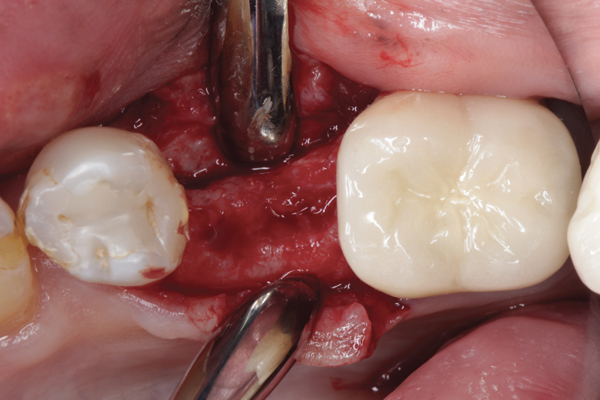

Fig 16. Radiograph of extraction socket. Buccal and lingual plates were defective.

Figure 16